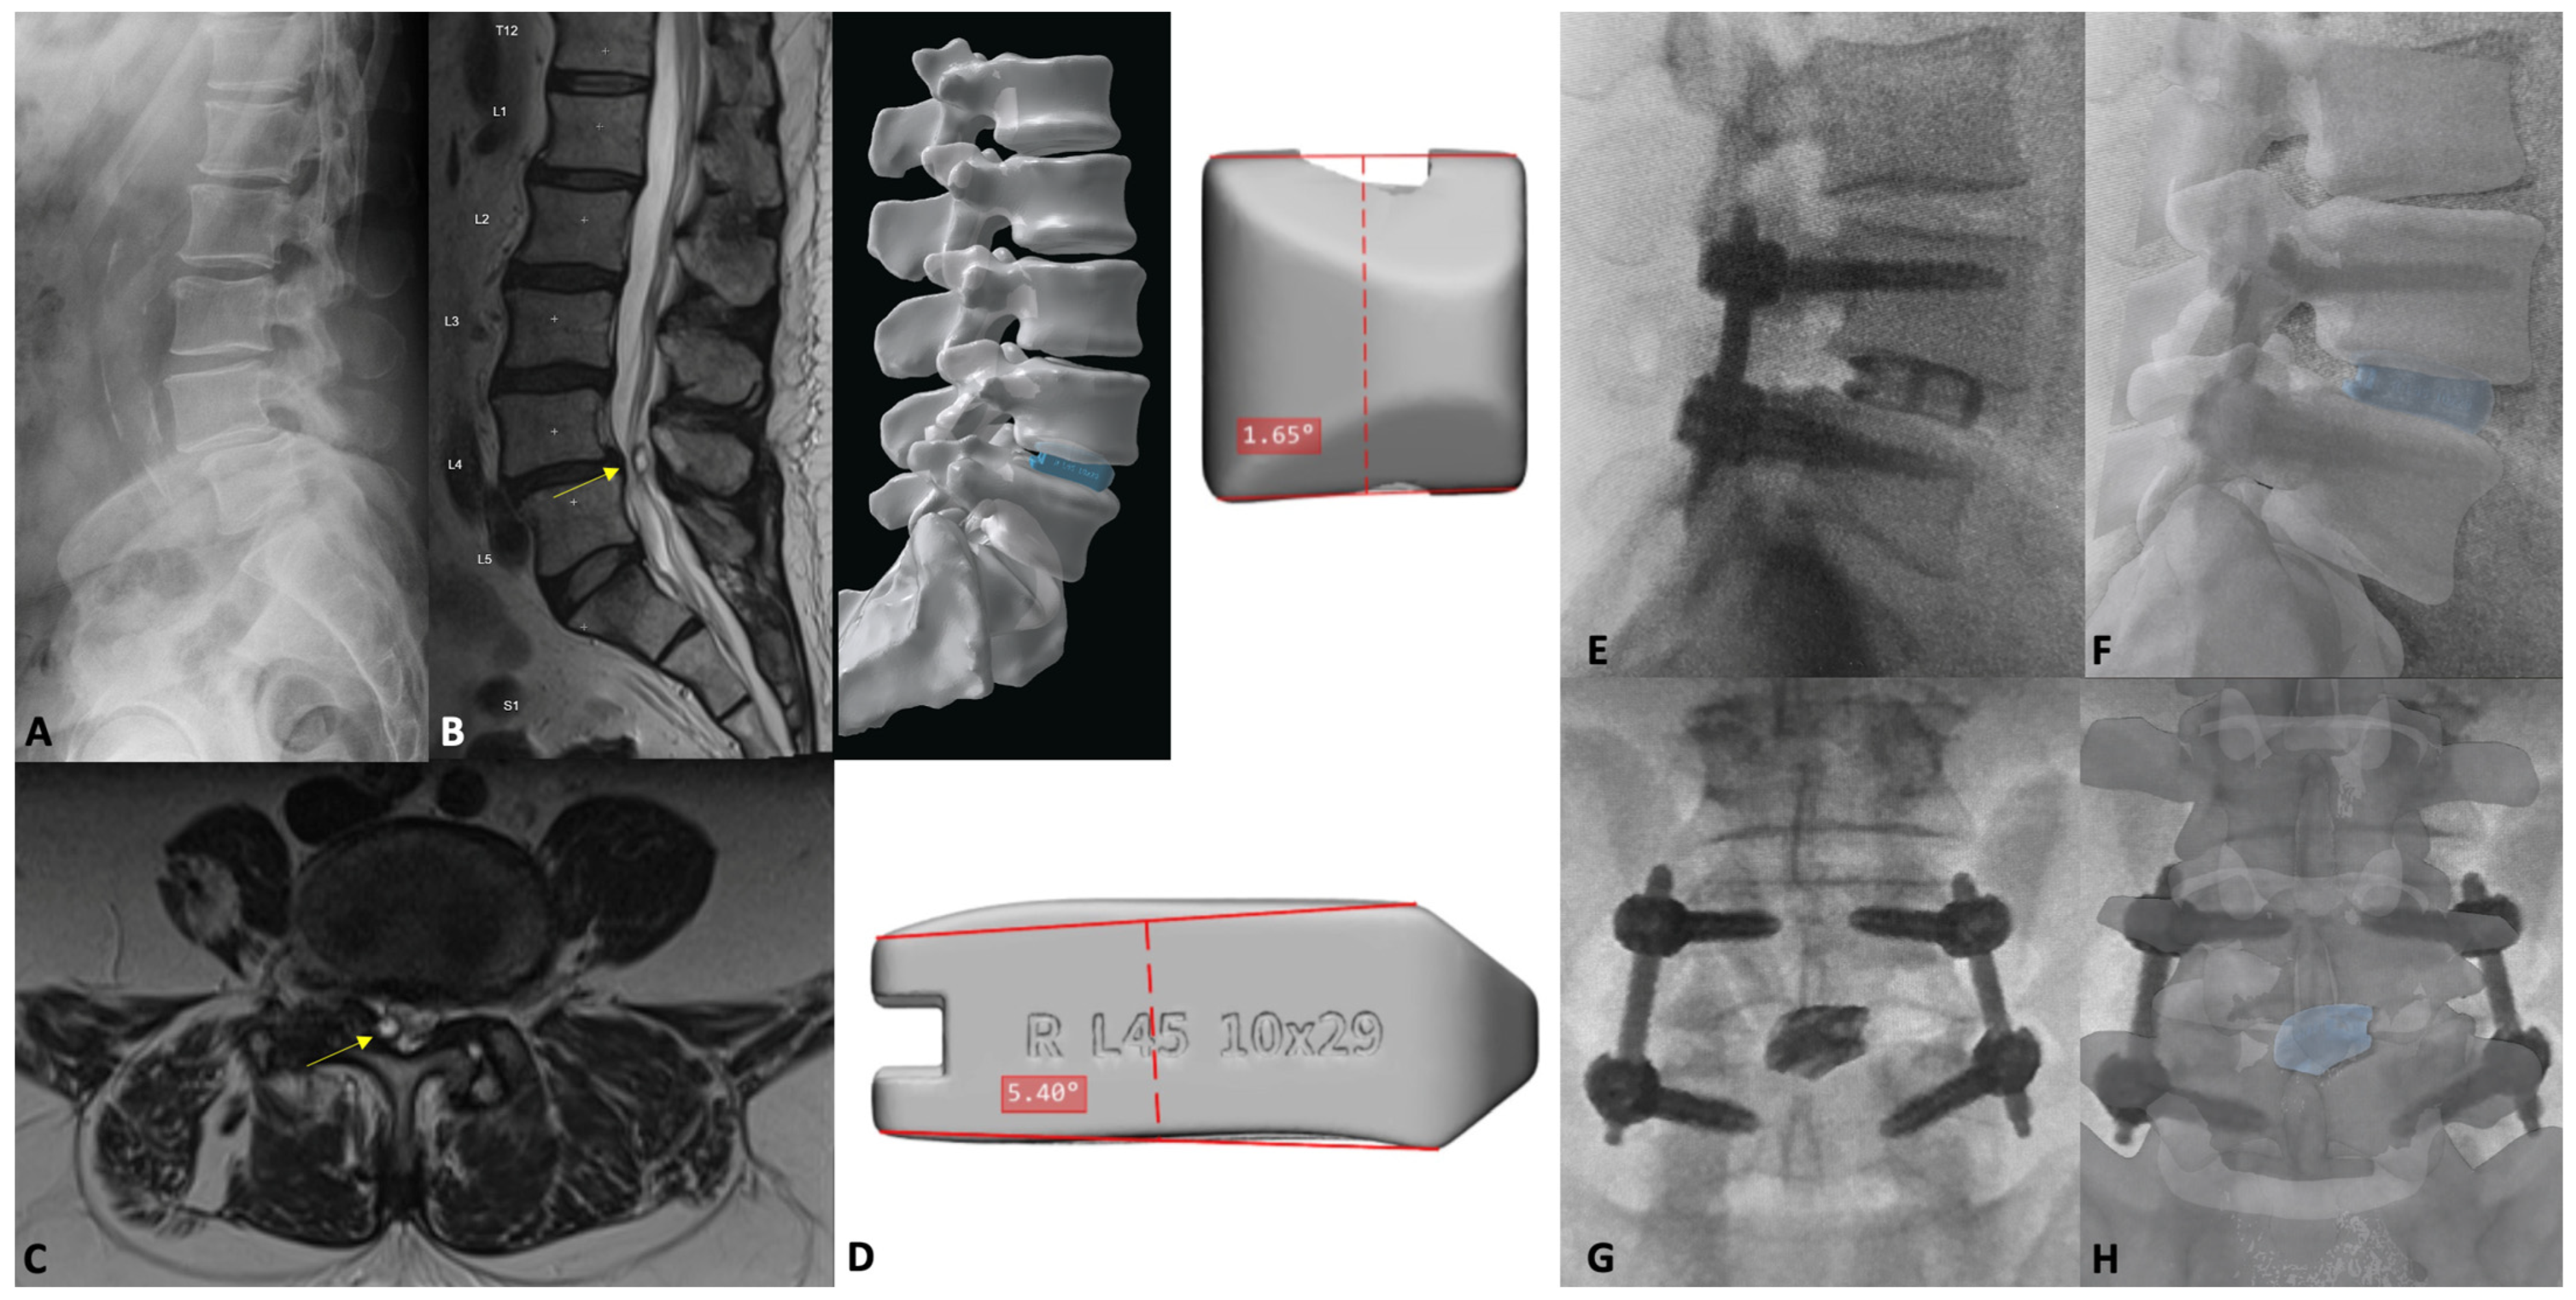

4. Minimally Invasive Transforaminal Lumbar Interbody Fusion

7.1. Introduction

7.3. Patient-Specific Implants